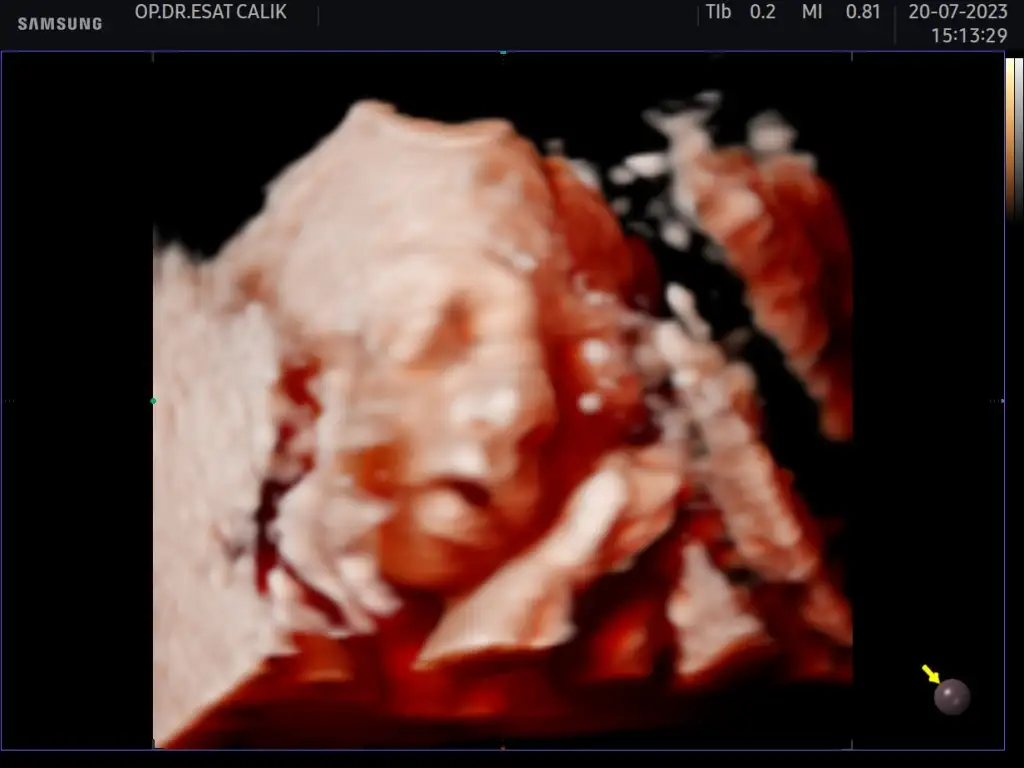

Yaa hatırlıyorum çok sevindimKızlar ben kendi memleketimdeki doktora gittim az önce. En son gittiğim doktor miyom kaynaklı iyi şeyler söylememişti bana. Bu gittiğim doktor da iyi bi doktor hatta bana miyomumun olduğunu ilk söyleyen doktordu, sizi baya korkutmuş ya falan diye tiye aldı o diğer doktoru. Bir önceki doktor miyom doğum kanalını kapatıyor demişti şimdi çok da kapatmıyormuş yeri biraz değişti sanırım, normal doğum bile olabilir falan dedi. Yani içimi rahatlatacak şeyler duydum çok iyi oldu Allah’a şükür inşallah öyle devam ederFotoğrafını da atayım size uyuyordu tabi ki yine eve geldik pıt pıt vuruyor şimdi

Çok güzel maşallah ya bazı doktorlar felaket tellalı gibi zaten çok sevindim senin adına rahat rahat bir hamilelik geçirirsin inşallahKızlar ben kendi memleketimdeki doktora gittim az önce. En son gittiğim doktor miyom kaynaklı iyi şeyler söylememişti bana. Bu gittiğim doktor da iyi bi doktor hatta bana miyomumun olduğunu ilk söyleyen doktordu, sizi baya korkutmuş ya falan diye tiye aldı o diğer doktoru. Bir önceki doktor miyom doğum kanalını kapatıyor demişti şimdi çok da kapatmıyormuş yeri biraz değişti sanırım, normal doğum bile olabilir falan dedi. Yani içimi rahatlatacak şeyler duydum çok iyi oldu Allah’a şükür inşallah öyle devam ederFotoğrafını da atayım size uyuyordu tabi ki yine eve geldik pıt pıt vuruyor şimdi